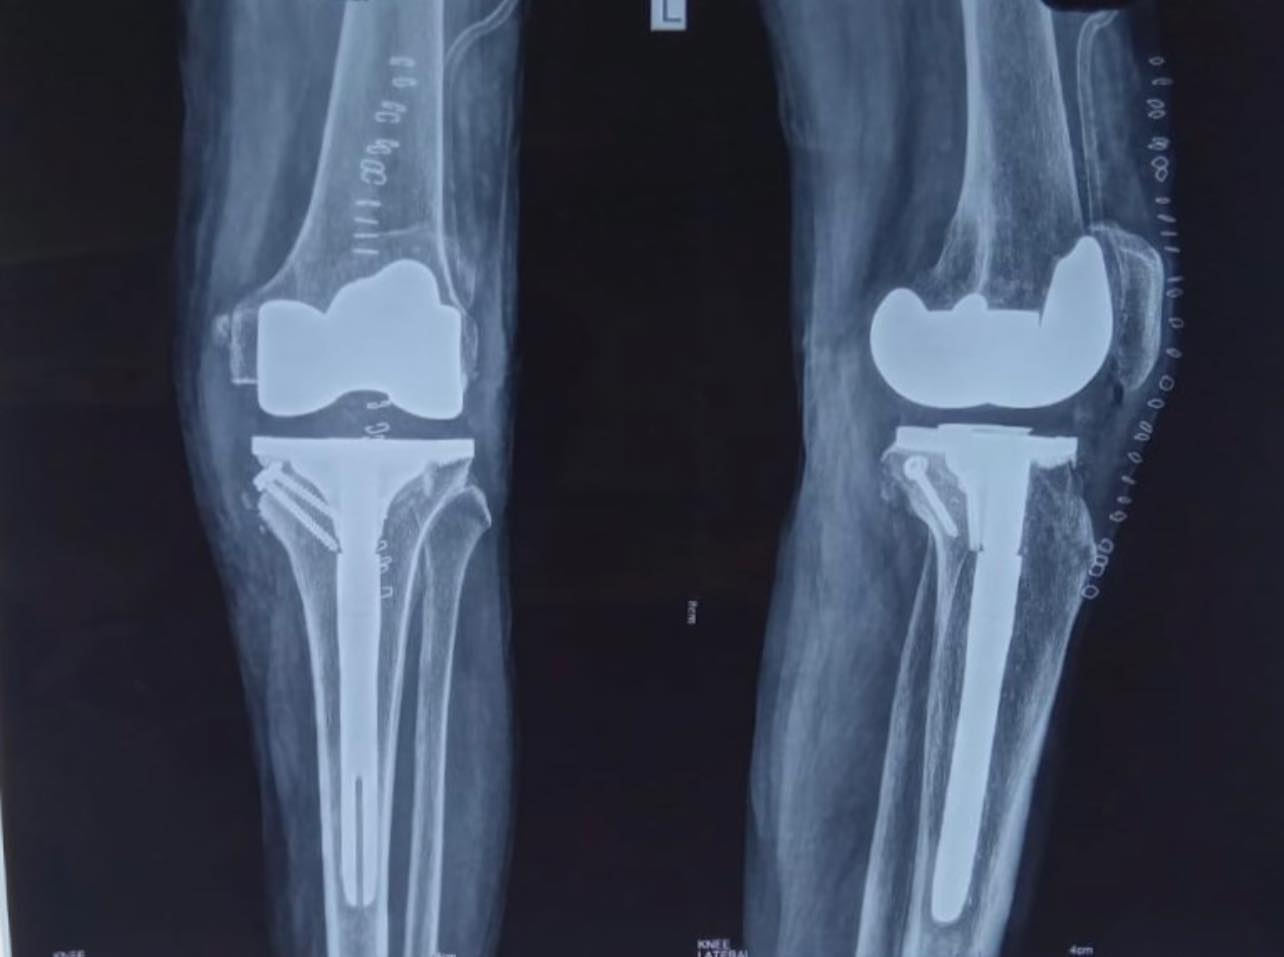

48-year-old male with windswept deformity of knees due to rheumatoid arthritis, both femoral lateral condyles are hypoplastic. Left tibia has a medial bone defect of 20 mm. Treated with long stem prostheses for tkr (total knee replacement) with semi-constrained liners. For the left knee bone defect, bone grafting was done with cc screw fixation.

In such extensively damaged knees it is important to keep all options in hand and pre-plan properly preferably on the computer to give optimum result.